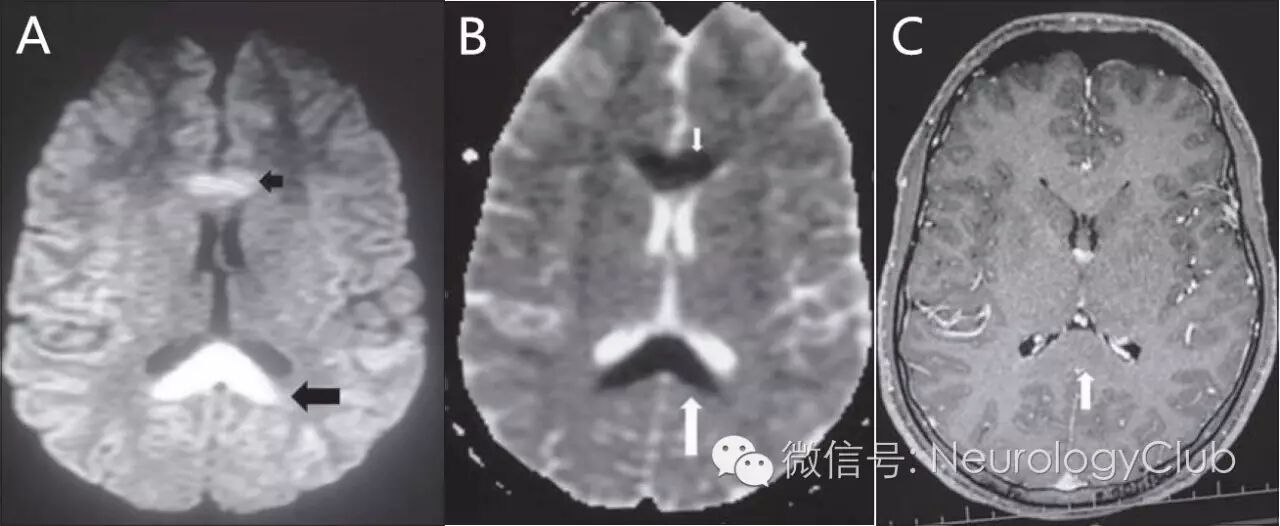

(图9:立克次体感染相关的RESLES。A:DWI;B:ADC;C:T1增强;可见SCC回旋镖征”及胼胝体膝部病灶)